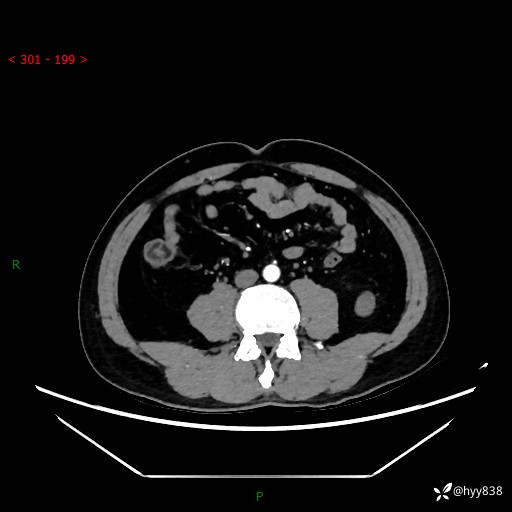

中年男性,左侧腰背部间断性胀痛不适。第一眼“乳头或囊肿”,有无意外---(有结果)

【患者信息】:41岁/男

【主诉】:左侧腰背部间断性胀痛不适1周

【现病史及既往史】:患者1周前无明显诱因出现左侧腰部疼痛,呈间断性胀痛,休息后可缓解,无放射痛,偶可见肉眼血尿,无血块,无尿频尿急尿痛,无夜尿增多,无畏寒发热、咳嗽咳痰等症状。于我院查双肾CT示:左肾占位性病变,左肾下极囊性病变,左肾轻度积水,胆囊多发结石。今为求进一步诊治来我院,门诊以“左肾占位性病变”收治入院。 起病以来,患者精神佳,饮食、睡眠良好,大便正常,小便如上诉,体力体重无明显变化。

【检查】:肾脏CT平扫+增强